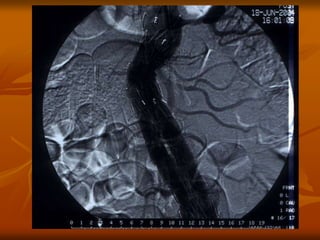

ENDOVASCULAR REPAIR

EVAR

Preoperative angiogram Postoperative angiogram

®

AAA repair with stent graft